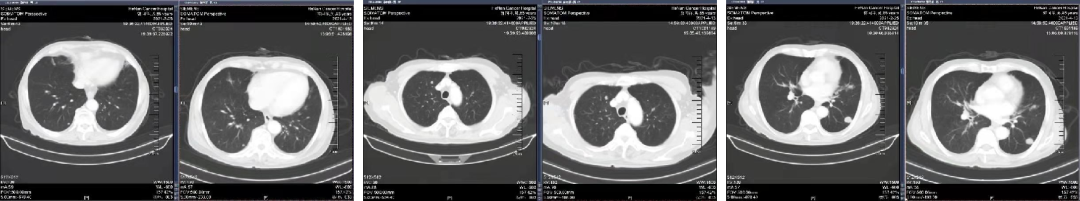

02 初诊病史

诊断:直肠腺癌双肺转移IV期,KRAS 突变型,MSS。高龄,患者及家属无手术意愿,全身系统治疗。

于2021.04.14 始行“曲氟尿苷替匹嘧啶片(TAS-102)+贝伐珠单抗”2周方案治疗至今。

04 疗效评估

患者疾病控制良好,耐受情况好。